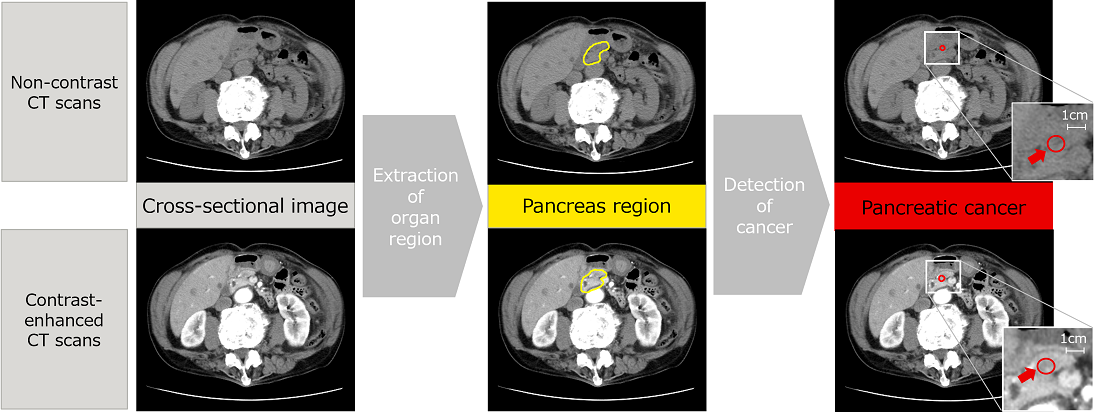

Pancreatic cancer is a disease that is difficult to detect in the early stages, and it has proven difficult to establish a technology capable of identifying cancers beyond all doubt and thereby increasing the opportunities for detection in the initial stages.

To address this problem, Fujitsu has been collaborating since April 2022 with the Southern TOHOKU General Hospital (*10) and others to promote the development of AI technology to detect pancreatic cancer from non-contrast CT scans, such as those widely carried out during general health checks and similar procedures.

Due to the low levels of contrast in non-contrast CT scans, it has always been difficult to identify the location of the pancreas and detect cancers. So, Fujitsu has used AI to develop a technology that estimates the continuity across adjacent cross-sectional scans, taking into account the patient’s anatomy. It automatically conducts three-dimensional analysis in areas with strong continuity in the images and planar analysis in areas with weak continuity. The results of evaluations of the CT scans from the Southern TOHOKU General Hospital show that locations where cancer is suspected in the pancreas area were successfully detected with 90% accuracy.

This AI technology is the result of the use of converging technologies (*11) that integrate Fujitsu’s image analysis technology with the clinical observations made by the Southern TOHOKU General Hospital, and is likely to make a significant contribution to improving the early discovery of pancreatic cancer. In 2023, this technology was unveiled to over 20,000 physicians and other participants at JDDW 2023 (*12), where it demonstrated the advanced level of the technology addressing social needs.